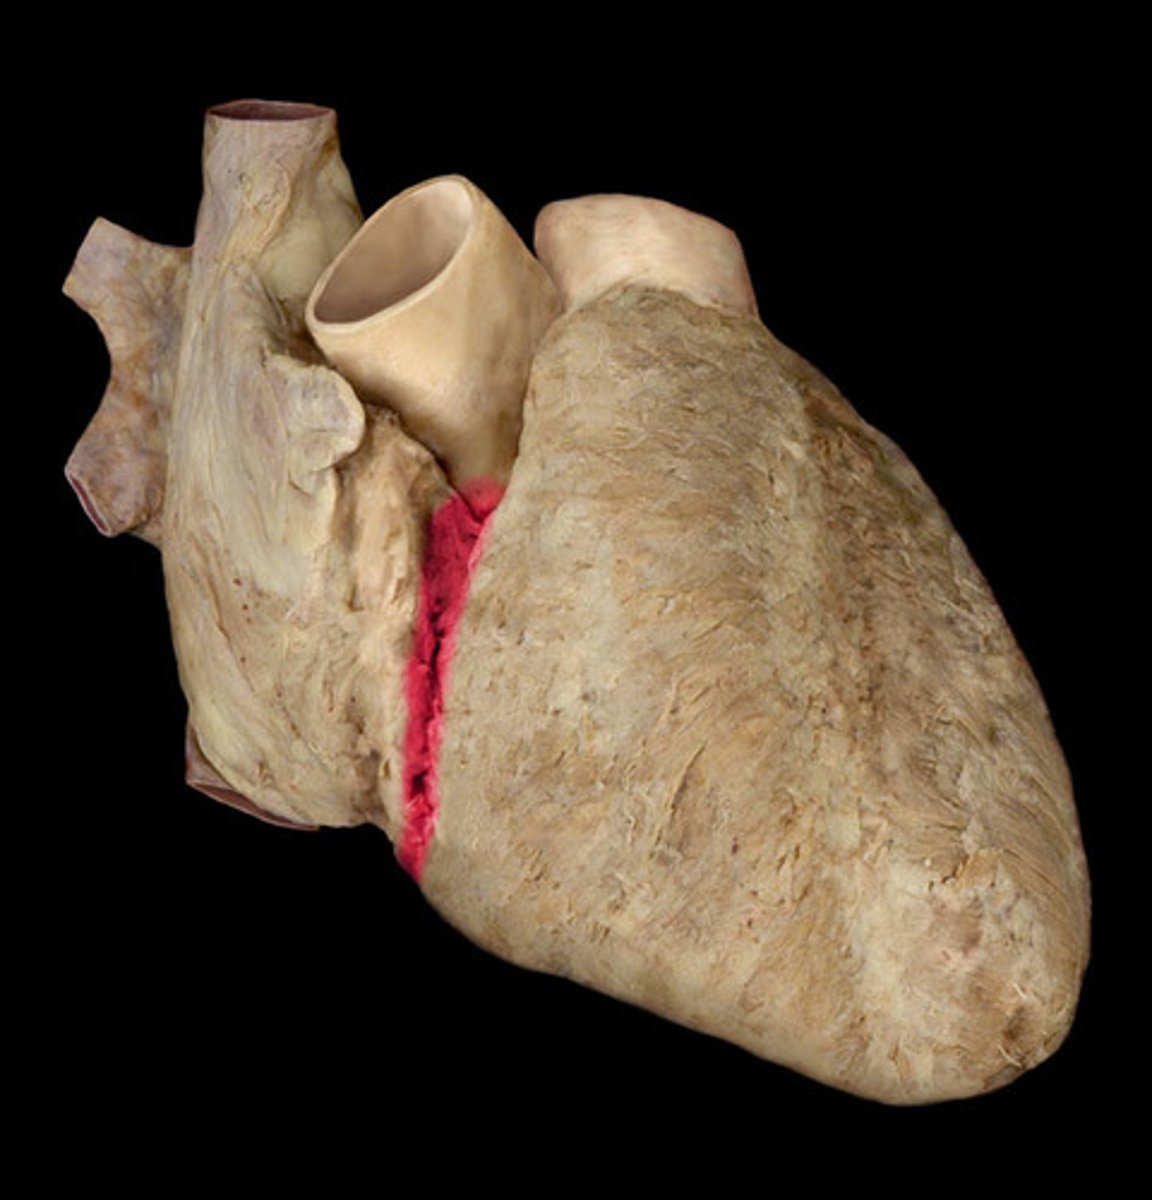

Coronary sulcus

Depression, goes from Right auricle to Left auricle, probe lays in

H1

anterior interventricular sulcus

Depression; divot on right side, anterior, by right ventricle

posterior interventricular sulcus

Depression; divot on right side, posterior, by right ventricle

R coronary artery

st

pull right auricle back to show tube on anterior side

16

R marginal artery

forms Y-shape off of coronary artery

1st branch off coronary artery

posterior interventricular artery

Structure; posterior side, crinkled ribbon in sulcus

22

anterior interventricular artery

Structure; sits in anterior sulcus, anterior side, curly tube

17

Circumflex artery

on left border of heart, curly

comes off L coronary arter

18